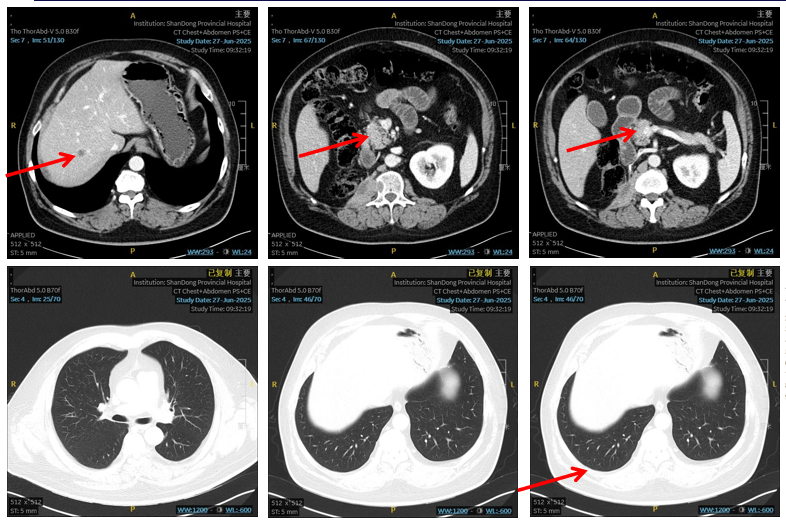

2025年6月27日 随访CT诊断意见:1. 近右侧膈肌脚、腰大肌处软组织肿块转移治疗后,较前缩小;2. 肝内及胰头区转移瘤治疗后,较前缩小;3. 双肺多发小结节,较前明显减少、缩小。根据RECIST 1.1标准,疗效评估为部分缓解(PR)。

图2 2025年6月27日CT复查

这种协同机制在本例中体现为“快速且深度的疗效”。从2025年4月4日启动治疗至6月27日评估,仅2个多月时间,患者右侧膈肌脚、腰大肌转移灶缩小,肝、胰头转移灶缩小,双肺转移结节明显减少、缩小,顺利达到PR,且全程无明显不良反应。